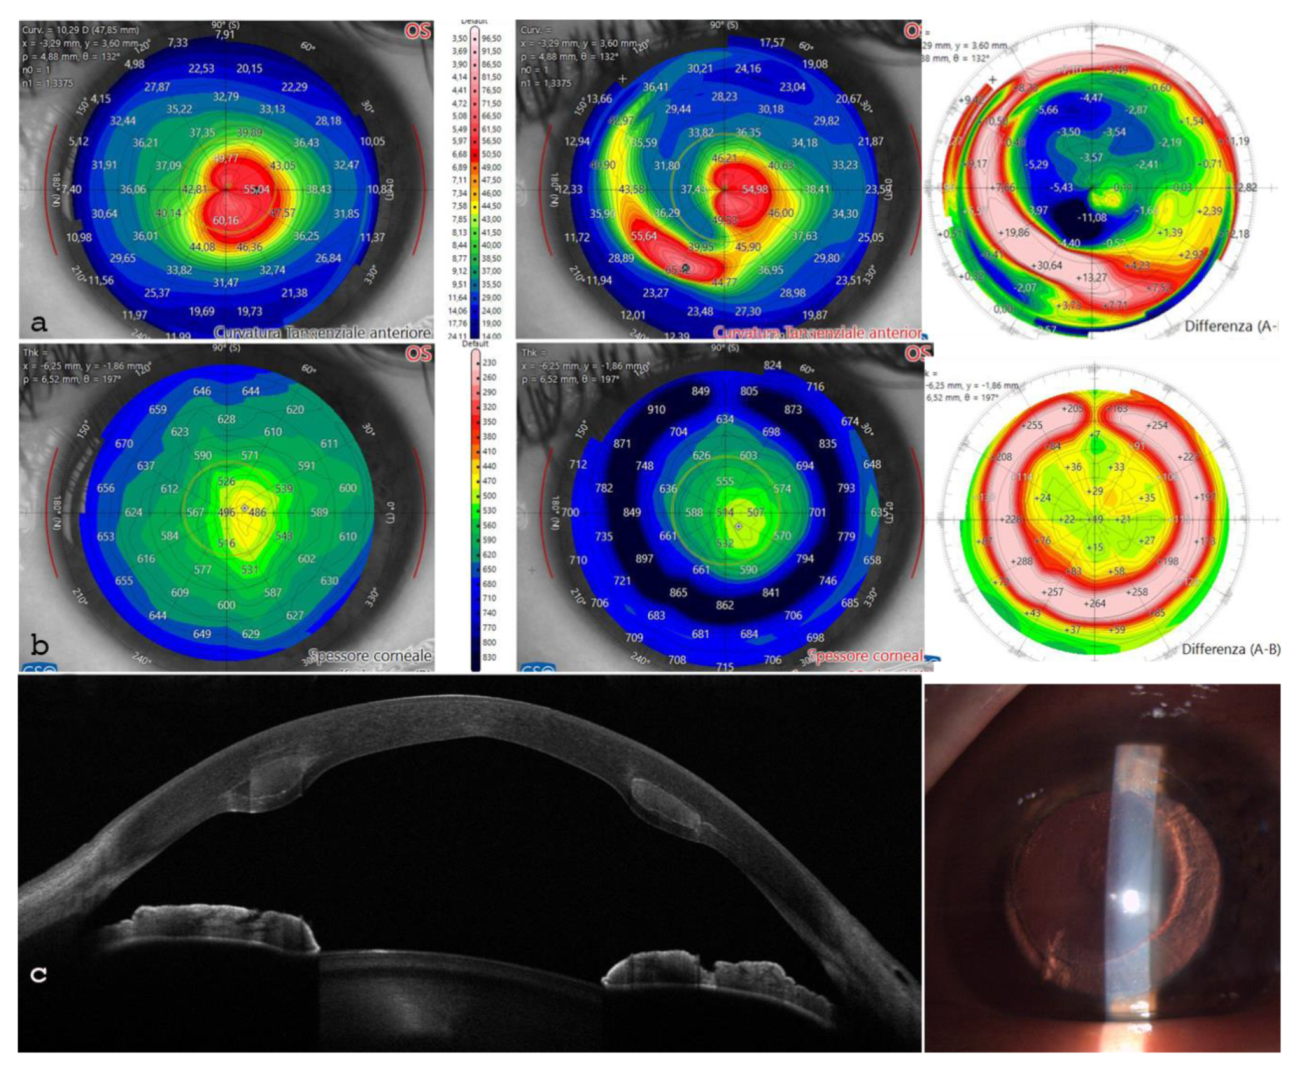

The patient achieved a BSCVA of 0.6 d eq. with a refraction of +2 sphere = -5.00 @ 180°. There was a significant reduction in K max from 62.4 to 54 D, accompanied by corneal remodeling and regularization of the tomographic profile. The thinnest point increased from 443 to 486 µm and the Sim K steep values were adjusted from 58.3 to 45.7 D as reported in Table 7.

Figure 10. 10 a: the anterior tangential topographic map shows corneal flattening and profile regularization. 10 b: the differential pachymetry map indicates the correct placement of the ACXL CAIRS. 10 c.: AS-OCT and slit-lamp images reveal the allogenic segments positioned at 65% planned stromal depth. .